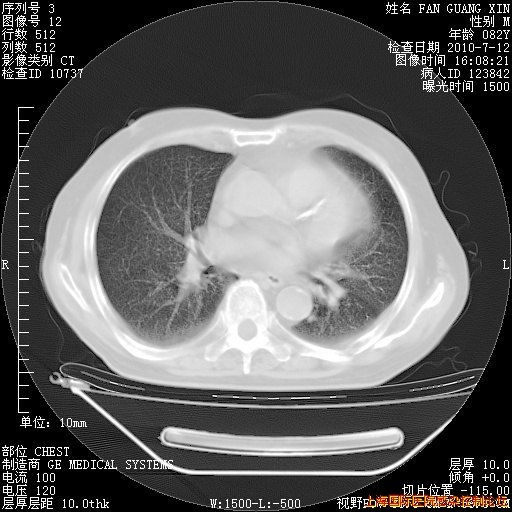

补发6月12日肺部CT肺窗

6月12日肺窗

整整相隔30天的肺部CT好像有所好转啊。甲强龙减量第3天,需要观察体温。

海管,自昨日你和我通完话后,不知您岳父消化道症状有无缓解?体温怎样?阅读7.12日胸部ct,个人认为目前激素治疗是有效的,甲强龙减量是适宜的。因在抗痨治疗,需密切观察肝功、肾功能和血常规。不过,老年、长期住院和大量使用激素,很担心菌群失调发生